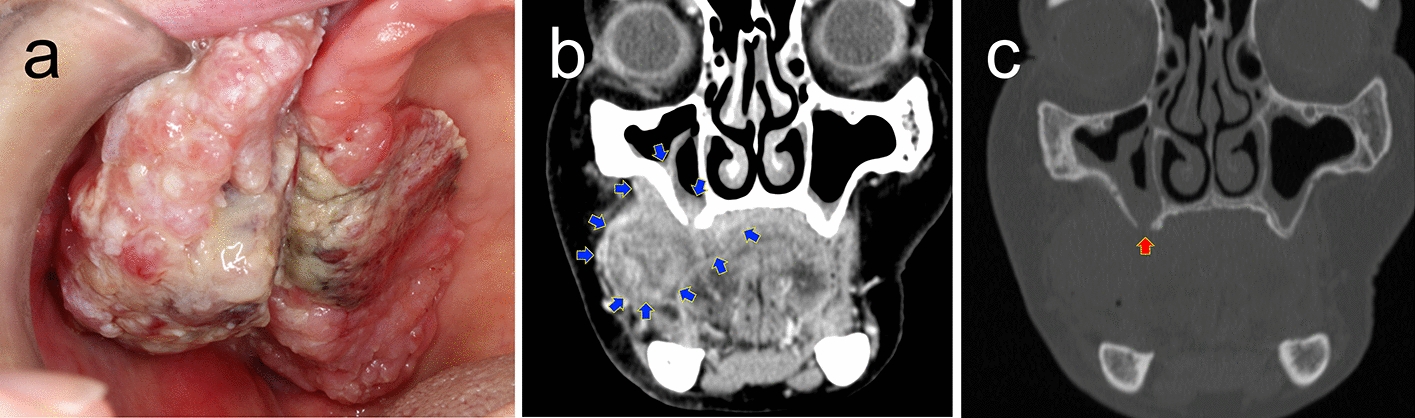

An 89-year-old female was referred to the Osaka University Dental Hospital for painful swelling in the upper right gingival region. The patient had noticed a gingival mass for 1 month and had no significant medical history. Intraoral examination revealed an approximately 60 × 40 mm lobulated mass with an ulcerative surface on the right maxillary posterior gingiva extending to the buccal mucosa (Fig. 1a). Computed tomography (CT) revealed an infiltrative lesion with maxillary bone resorption (Fig. 1b, c). With a provisional diagnosis of SCC, an incisional biopsy was performed (Fig. 2) followed by segmental maxillectomy (Fig. 3). The tumor recurred after 3 months, and the patient died 8 months after surgery due to complications related to disease recurrence (Table 1).

Fig. 1

Clinical presentation. a Intraoral finding. Representative coronal computed tomography (CT) images with bone window (b) and with contrast-enhanced (c). The blue arrows indicate a large tumor extension (b). The red arrow indicates a bone penetration at the alveolar process of the right maxilla (c)